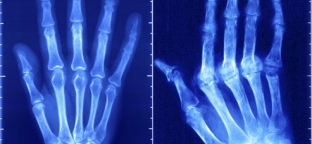

Причины такого заболевания как ревматоидный артрит по сей день остаются неизвестными. Однако увеличение количества лейкоцитов в крови и повышение скорости оседания эритроцитов указывают на то, что природа процесса является инфекционной. Ученые вплотную приблизились к созданию наиболее эффективного средства для борьбы с этим недугом.

Предположительно заболевание может развиваться в связи с инфекцией, которая вызывает нарушения иммунной системы у генетически предрасположенных лиц.

Заболевание влечет за собой высокий риск инвалидности (70%), наступающей довольно рано. Смерть от данной болезни возможна в основном от инфекционных осложнений и почечной недостаточности. Первое проявление ревматоидного артрита может наступить после тяжелой физической нагрузки, утомления, шока, а также в период гормональной перестройки организма.